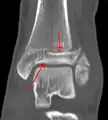

A triplane fracture of the ankle as seen on CT

CT

CT scans may be indicated when there is concern for a highly comminuted fracture or a fracture involving the joint surface.[9] This imaging may be used for surgical planning.